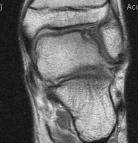

Some patients also have pain at the front of the ankle when they walk, caused by spurring at the front of the ankle joint. Ankle arthroscopy can be useful to remove this spur, and improve patient’s pain when walking.